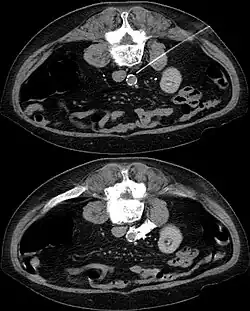

In CT guided lumbar sympathicolysis, the site of neurolytic solution injection is chosen at the level of L2-L3 vertebra level. The needle should avoid the vertebral transverse process, ureter, pelvicalyceal system, and other major blood vessels. The target injection site would be anteromedial to the psoas muscle and dorsolateral to the abdominal aorta, where the sympathetic trunk would most likely be located.[1]

After the skin of the puncture site is cleaned, 2% lignocaine is injected into the to numb the skin and also the needle trajectory. Then a 22G China needle is inserted into the target site, which is bounded by the vertebral body, aorta, inferior vena cava, and psoas muscle. This region houses the lumbar sympathetic ganglion. Then, iodinated contrast medium (iohexol) and lignociane is injected into the target site to check the position of the needle tip. Once the needle tip position is confirmed, a mixture of neurolytic solution (99.9% alcohol) and iodinated contrast medium (at a ratio of 10:1) is injected into the target site.[1]